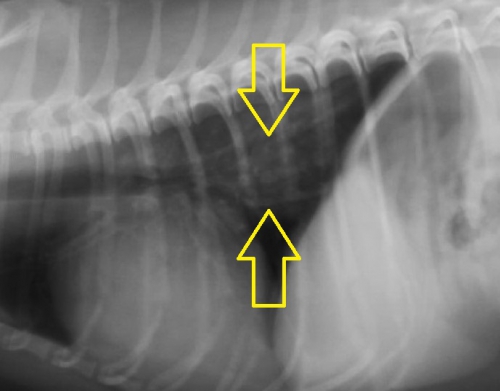

”ジャーキーを食べた直後”ということと、診察室での様子からやはり食道の異物が疑い、頸部のレントゲン検査に加えて、確定診断のためにバリウムによる食道造影を実施したのが下写真です。

頸部レントゲンで、「異物が存在する」はずの黄色の丸で囲んだエリアには異常は認められません。

ここでバリウム造影検査を行ったものが下写真です。上の写真黄色のサークル内でほぼ見えない異物が造影剤で浮かび上がっているのがお分かりだと思います。異物は咽頭のすぐ下から食道に入って数センチ以内の場所に存在しているようです。